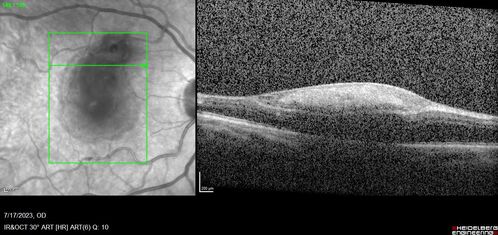

Retinal Arterial Macroaneurysm with pre-retinal hemorrhage

72 year old female who takes Xarelto had sudden vision loss while moving heavy furniture.  VA was 20/200.  The lesion has preretinal blood but later rebled with subretinal blood, was lasered and the final vision was not very good but the patient was lost to follow-up at 3 months